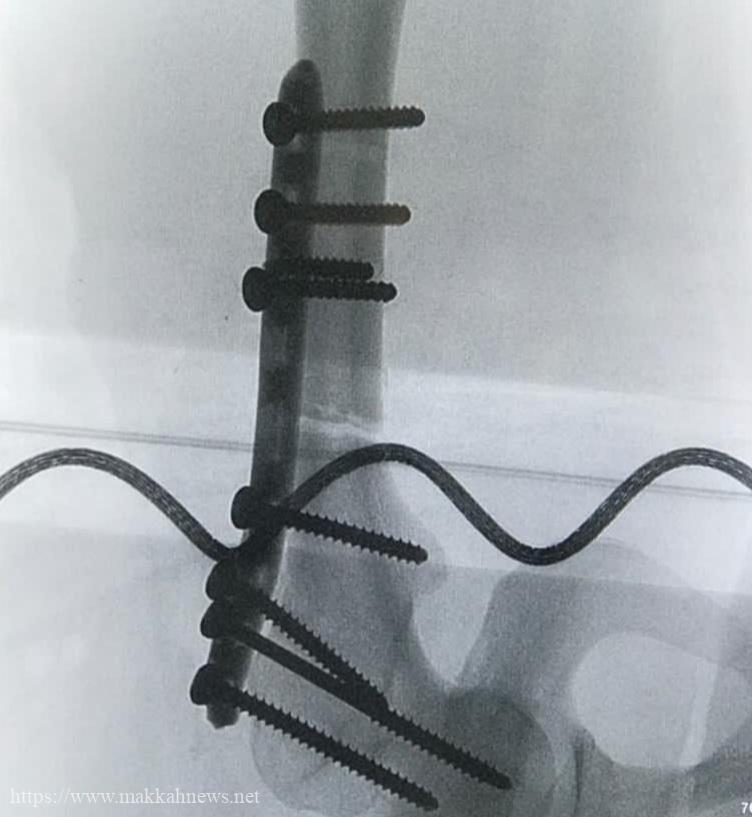

جراحة معقدة لحالتي العظم الرخامي في مستشفى الدوادمي العام

(مكة) فوزية الفواز _ الرياض _ نجح مستشفى الداودمي العام في اجراء عمليتين نادرة و معقدة لتثبيت كسور الفخذ لمصابيّن…